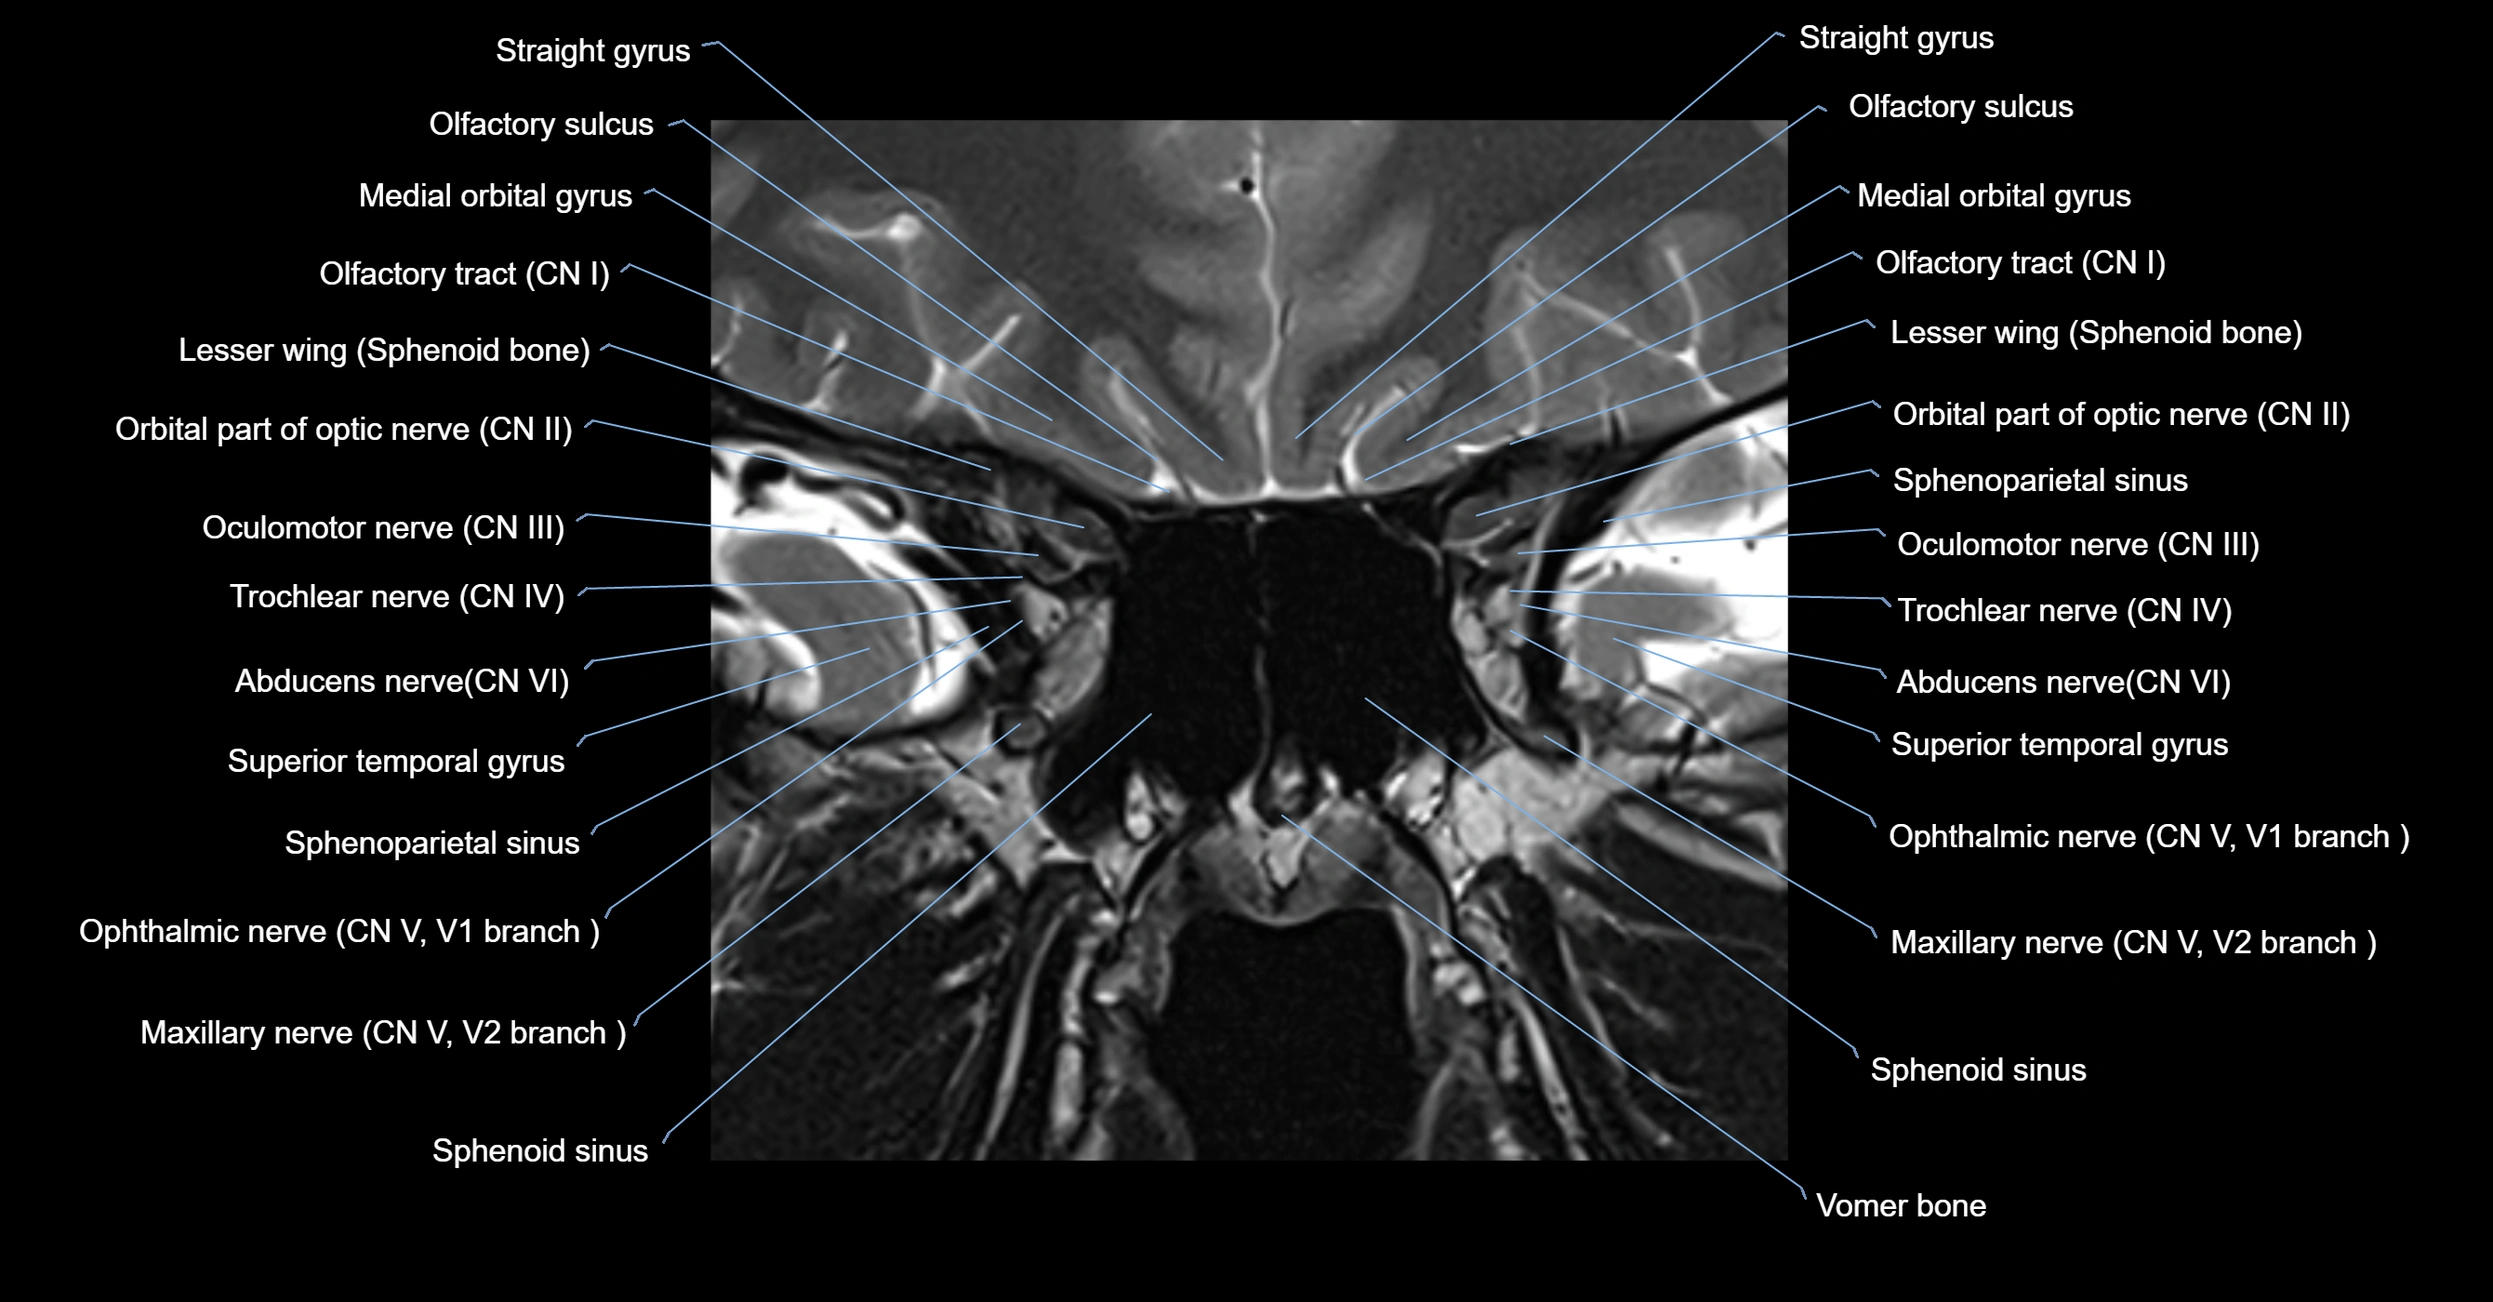

MRI Appearance

The abducens nerve is a small, thin, linear structure

Best visualized on high-resolution T2-weighted 3D MRI sequences (e.g., FIESTA or CISS)

Seen as a hypointense (dark) line running from the brainstem at the pontomedullary junction, traversing the prepontine cistern, and entering Dorello’s canal under the petrosphenoidal ligament, then into the cavernous sinus, and finally the orbit

May be challenging to visualize in standard MRI due to its small size

Pathology may be inferred by absence, displacement, or enhancement of the nerve

MRI images